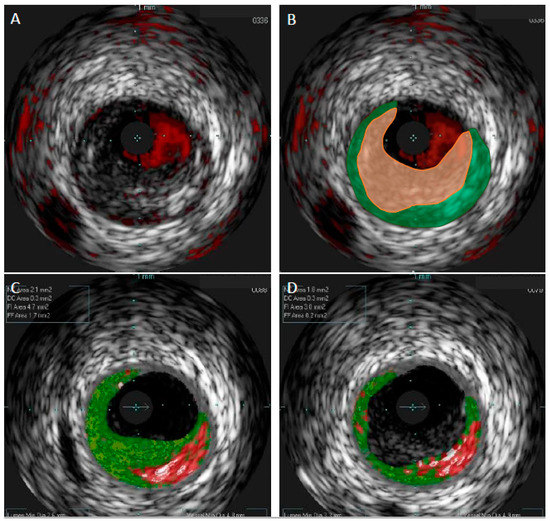

Although VH-IVUS allowed for more detailed identification of plaque composition as compared to GS-IVUS, the need for even more detailed evaluation of coronary lesions prompted the introduction of a new modality—near-infrared spectroscopy (NIRS). Spectroscopic analysis of the backscattered light emitted by an NIR probe provides information about the cholesterol content in the arterial wall [39]. The analysis of NIR is presented as a chemogram—a color-coded map showing the probability of the presence of the lipid-rich plaque with the yellow color meaning the highest probability (≥98%) [20]. A measure of the lipid burden in the atherosclerotic plaque is provided as lipid core burden index (LCBI): number of yellow pixels on the chemogram divided by all pixels and then multiplied by 1000 (Figure 3).

Figure 3.

Representative image of near-infrared spectroscopy and intravascular ultrasound (NIRS-IVUS) of lipid-rich plaque.